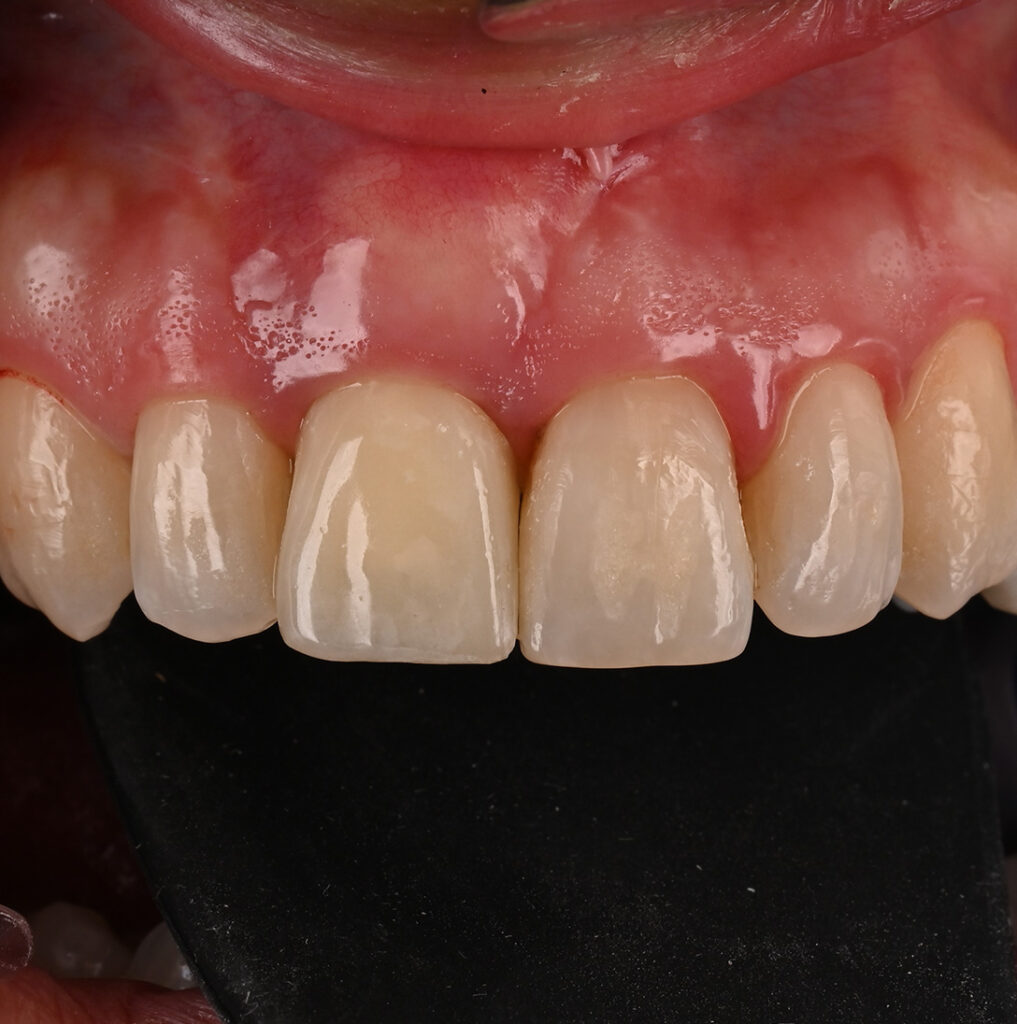

Step 3: Restoring Your Smile – Beautiful, Natural, and Yours

Once your implant has healed, the final step is attaching the custom-made crown. This completes your smile, and we’ll make sure it blends perfectly with your natural teeth.

What to expect: A seamless transition from the implant to your new tooth, restoring your confidence and function without any discomfort. You’ll leave the clinic with a smile you can feel proud of—without any of the fear or worry you might have started with.

- Artistic Excellence: We understand that an implant must do more than just chew; it must look perfect. Our focus on aesthetic dentistry ensures your new crown is a masterpiece of color, shape, and translucency.